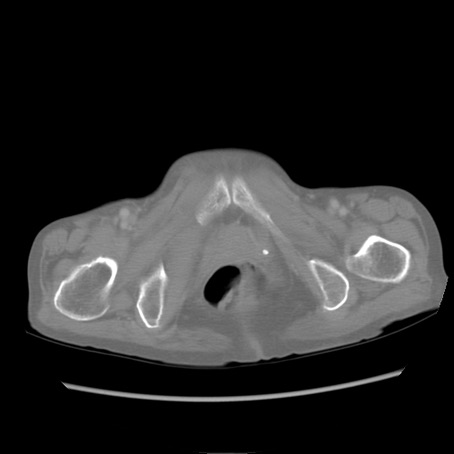

症例25(横断像)

【症例】80歳代女性

【主訴】胸のつかえ感

【現病歴】約9時間前に食後から胸のつかえた感じあり、嘔吐あり、来院。

【既往歴】胃癌(全摘)、胆摘、虫垂炎

【身体所見】心窩部に圧痛あり、反跳痛なし。

【データ】WBC 5700、CRP 0.05